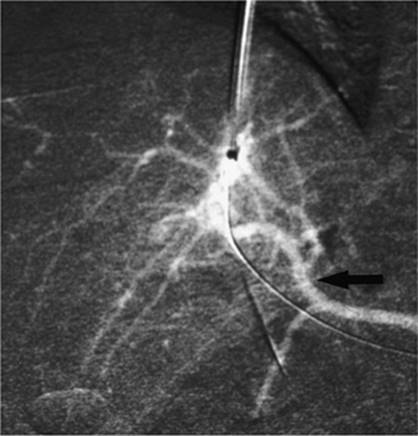

000193

Figure 35.6. Ultrasound image showing typical appearance for thoracentesis guidance. The central target (pleural effusion) is identified by an asterisk, lung margin by arrowheads, and drainage catheter pathway with an arrow.